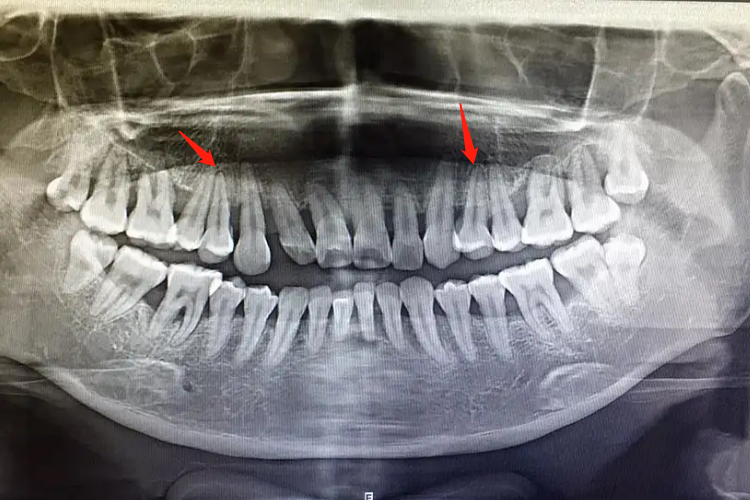

牙槽骨吸收轻重度可通过X线片观察,可见牙齿根尖处高度存在程度不一的下降。

牙槽骨吸收程度可以通过X线片来观察,骨吸收轻度时表现为牙槽嵴顶的硬骨板消失,或嵴顶模糊呈血蚀状。嵴顶的少量吸收使前牙的牙槽间隔由尖变平或凹陷,在后牙则使嵴顶由宽平变凹陷,以后牙槽骨高度降低。牙槽骨重度吸收时,X线片可见根尖区有圆形或椭圆形的骨质疏松投影区,牙槽骨高度下降,严重时可达下降2/3。